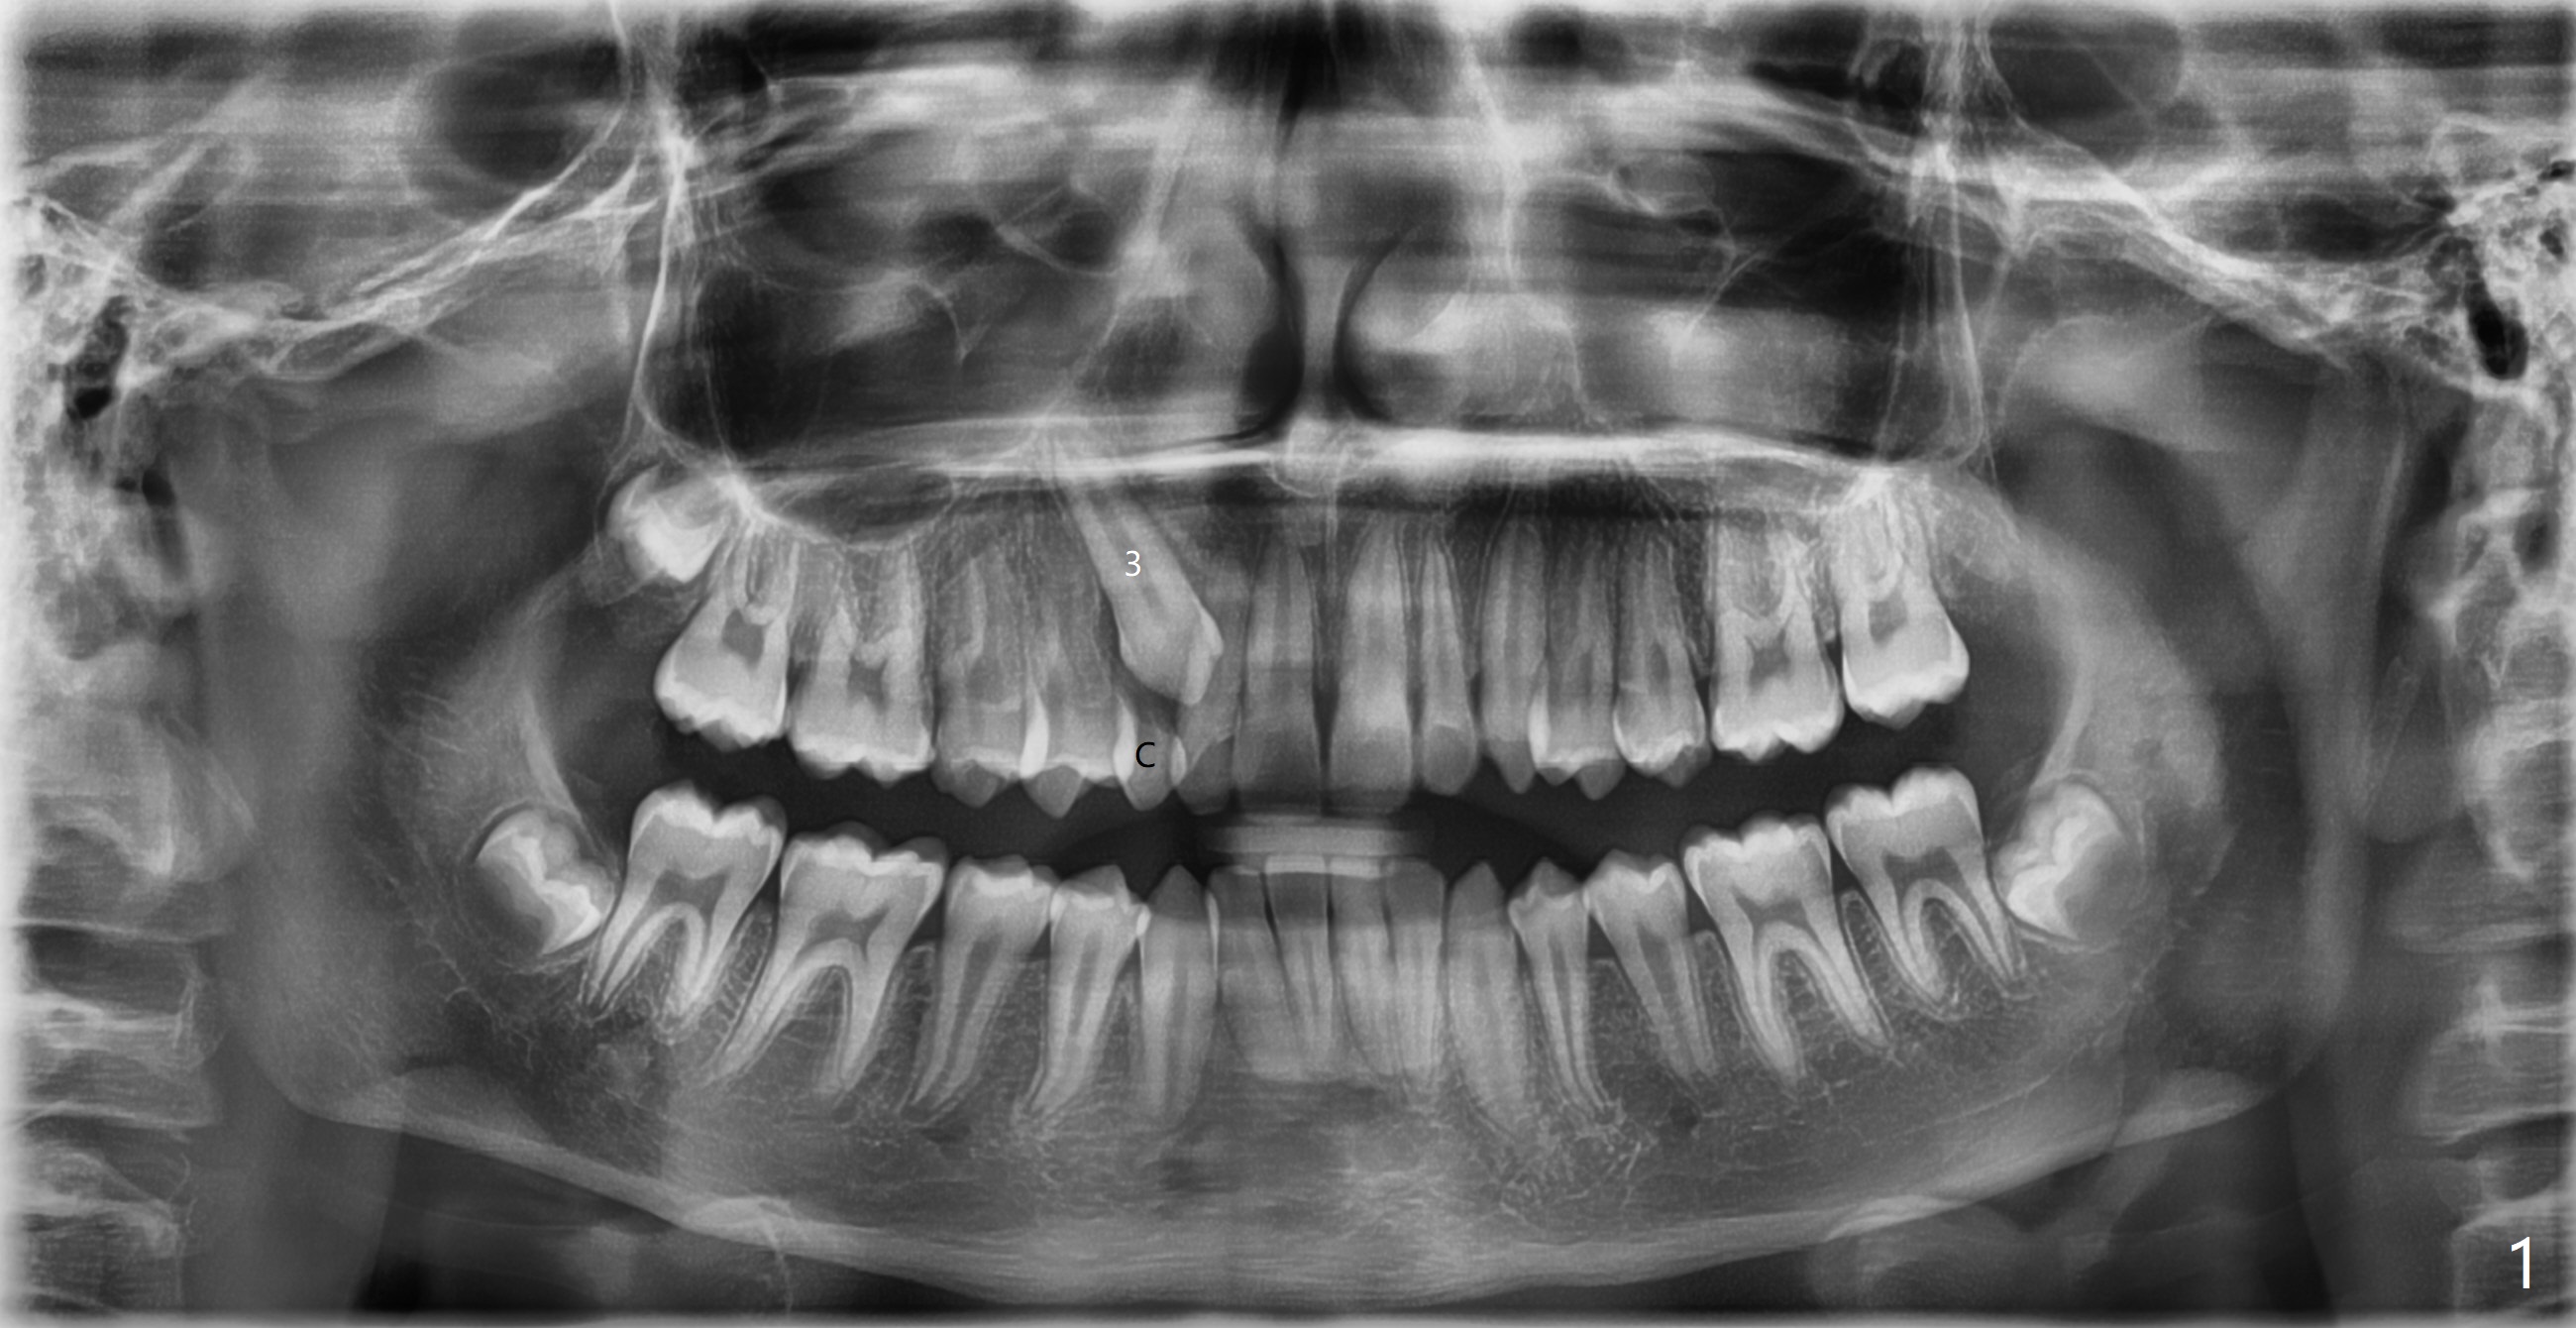

Impacted

Canine

A 12-year-10-month-old man presents to clinic for new patient examination. The upper right deciduous canine retains while the upper left permanent canine has erupted. His profile is normal. What is sequence of diagnosis and treatment?